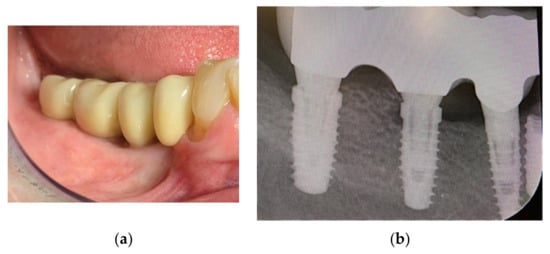

A CBCT scan was made with an initial setup for guided surgery, demonstrating a bone height less than 4 mm from the mandibular canal (Figure 2 and Figure 3a,b).

Figure 2.

Panoramic radiograph showing the implant planning and nerve position.

Figure 3.

Position of the CBCT slice (a) showing the exact location of the canal (b).

Due to the severe atrophy in the posterior mandible, different treatment options were discussed with the patient, and after agreement, informed consent was signed, including all the different potential risks and complications. The patient was extensively informed about vertical bone augmentation utilizing an allograft Customized Bone block (Puros® Allograft Customized Bone Block, Zimmer-Biomet Dental, Palm Beach Gardens, FL, USA) to reconstruct the lost hard tissue volume in the vertical and horizontal dimensions. Based on the CBCT evaluation and the implant position, the exact size of the block was determined (Figure 4a,b).

Figure 4.

(a,b) Bone block design.